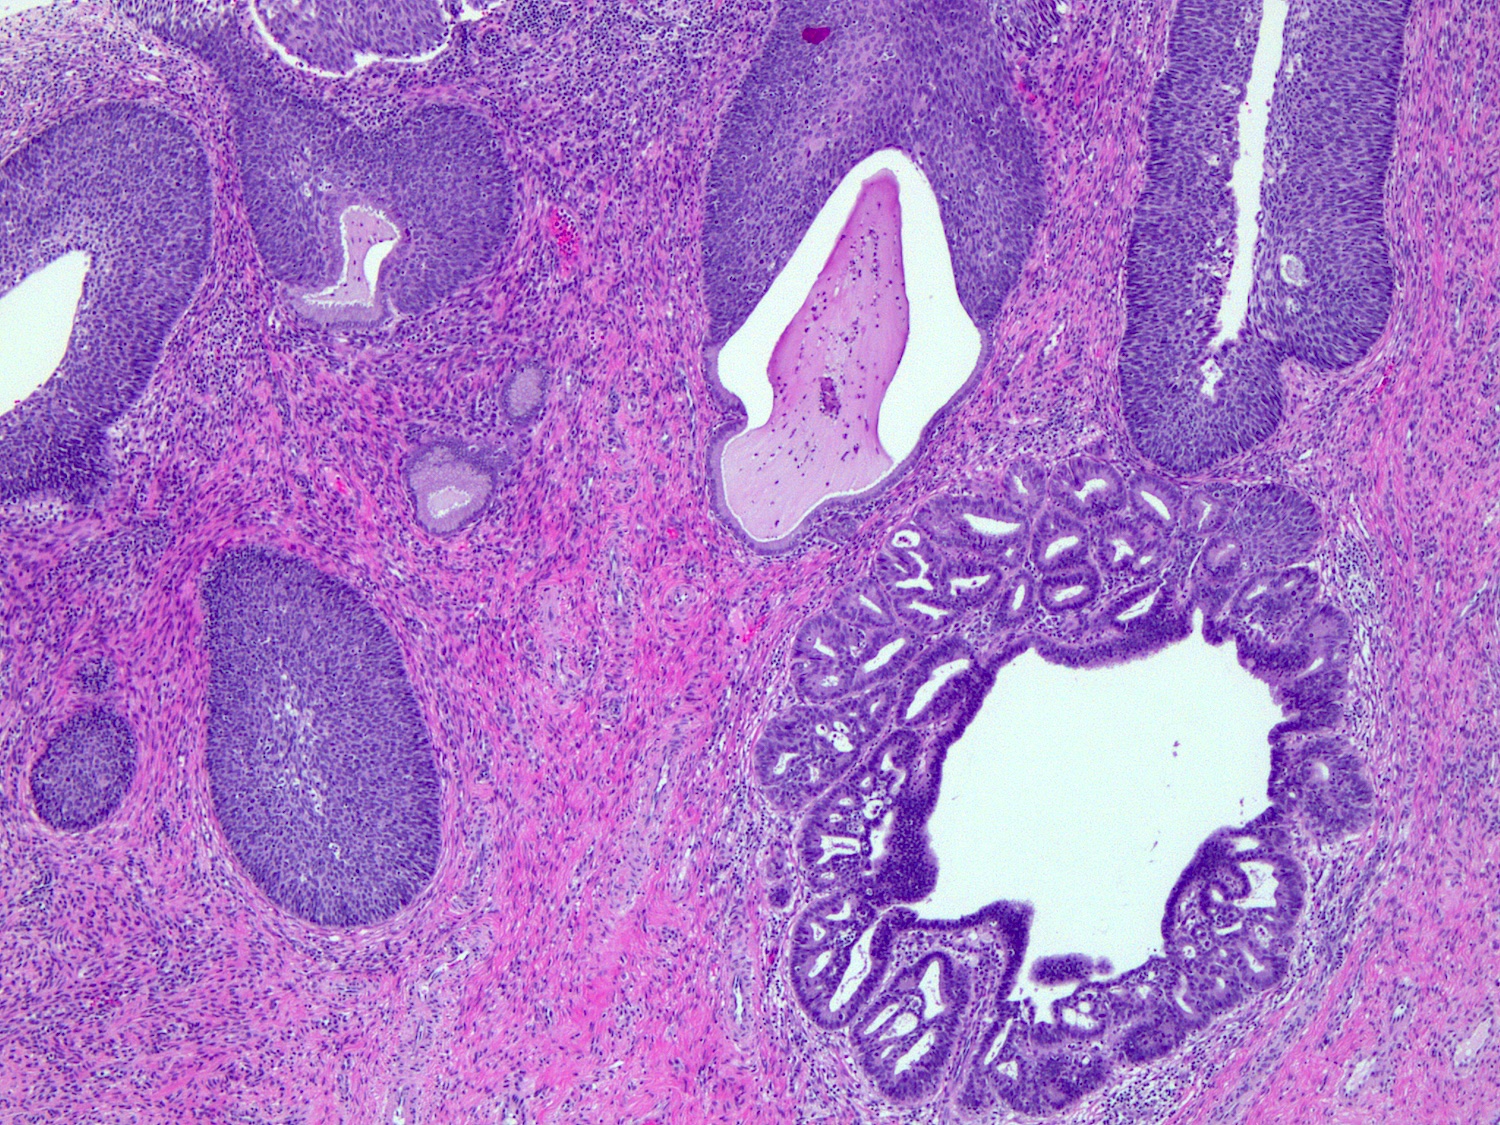

Microscopic (histologic) description

• Replacement of normal epithelium on the endocervical surface and in pre-existing endocervical glands with preservation of the normal endocervical architecture (comparison with the uninvolved cervix is often useful)

• Abrupt transition from normal to atypical epithelium from gland to gland and within individual glands

• Skip lesions are often seen

• Common partial gland involvement or surface epithelial involvement

• No desmoplastic stromal reaction and minimal inflammatory infiltrate

• Additional variable histologic features depending on type

• HPV related

• Usual (conventional) type

• Rarely cribriform or papillary intraglandular growth patterns

• Variable amounts of apical eosinophilic to mucinous cytoplasm

• Enlarged, fusiform, hyperchromatic, pseudostratified nuclei with irregular, coarse chromatin and occasionally with prominent nucleoli

• Frequent mitotic figures, often apical or “floating”

• Frequent apoptotic bodies

Glands with crowding and stratification

Abundant mitosis and apoptosis

AIS with adjacent uninvolved glands

Transition to AIS